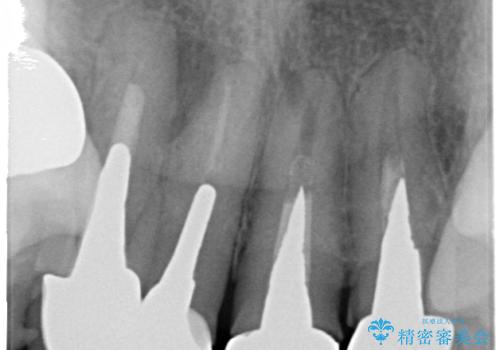

- 20年前に治療した前歯のセラミッククラウンが老朽化し見た目の改善を求めて来院されました。

不十分な根管治療を含めたセラミッククラウンのやりかえ治療を計画します。